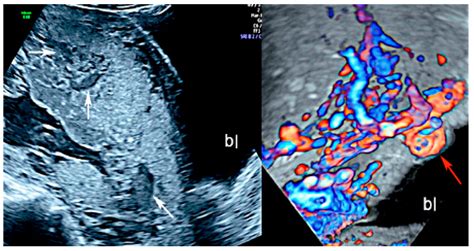

Prenatal care for COVID-19-positive mothers should be enhanced to monitor both maternal and fetal health closely. This may include:

• Frequent ultrasound examinations to assess fetal growth and development.

• Regular monitoring of maternal vital signs and symptoms.

• Close collaboration with a multidisciplinary team, including obstetricians, neonatologists, and infectious disease specialists.